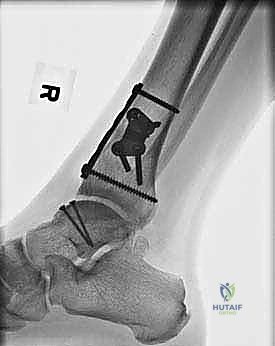

- التصوير بالأشعة السينية (X-rays): الخطوة الأولى لاستبعاد الكسور الكبيرة وتقييم المحاذاة العامة للعظام. قد تظهر الأشعة السينية الآفات الكبيرة، لكنها غالباً ما تفشل في إظهار التلف الغضروفي المبكر.

- التصوير المقطعي المحوسب (CT Scan): ضروري جداً للآفات الكبيرة. يوفر الـ CT صورة ثلاثية الأبعاد للعظم، مما يساعد الجراح في التخطيط الدقيق لعملية قطع العظم وحجم الطعم المطلوب زراعته.